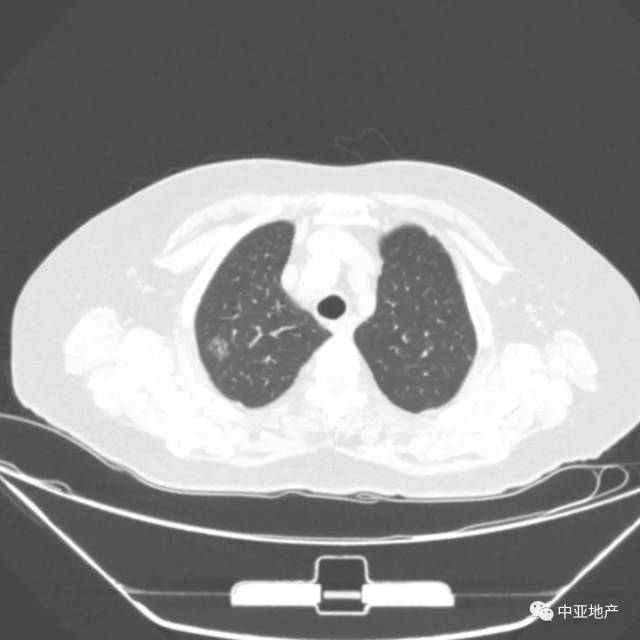

肺癌影像图片早期

肺癌影像图片早期,肺癌影像图片晚期

囊腔样肺癌的影像特征和鉴别诊断

【病例】早期肺癌2例ct影像

右肺上叶磨玻璃结节,早期肺癌.